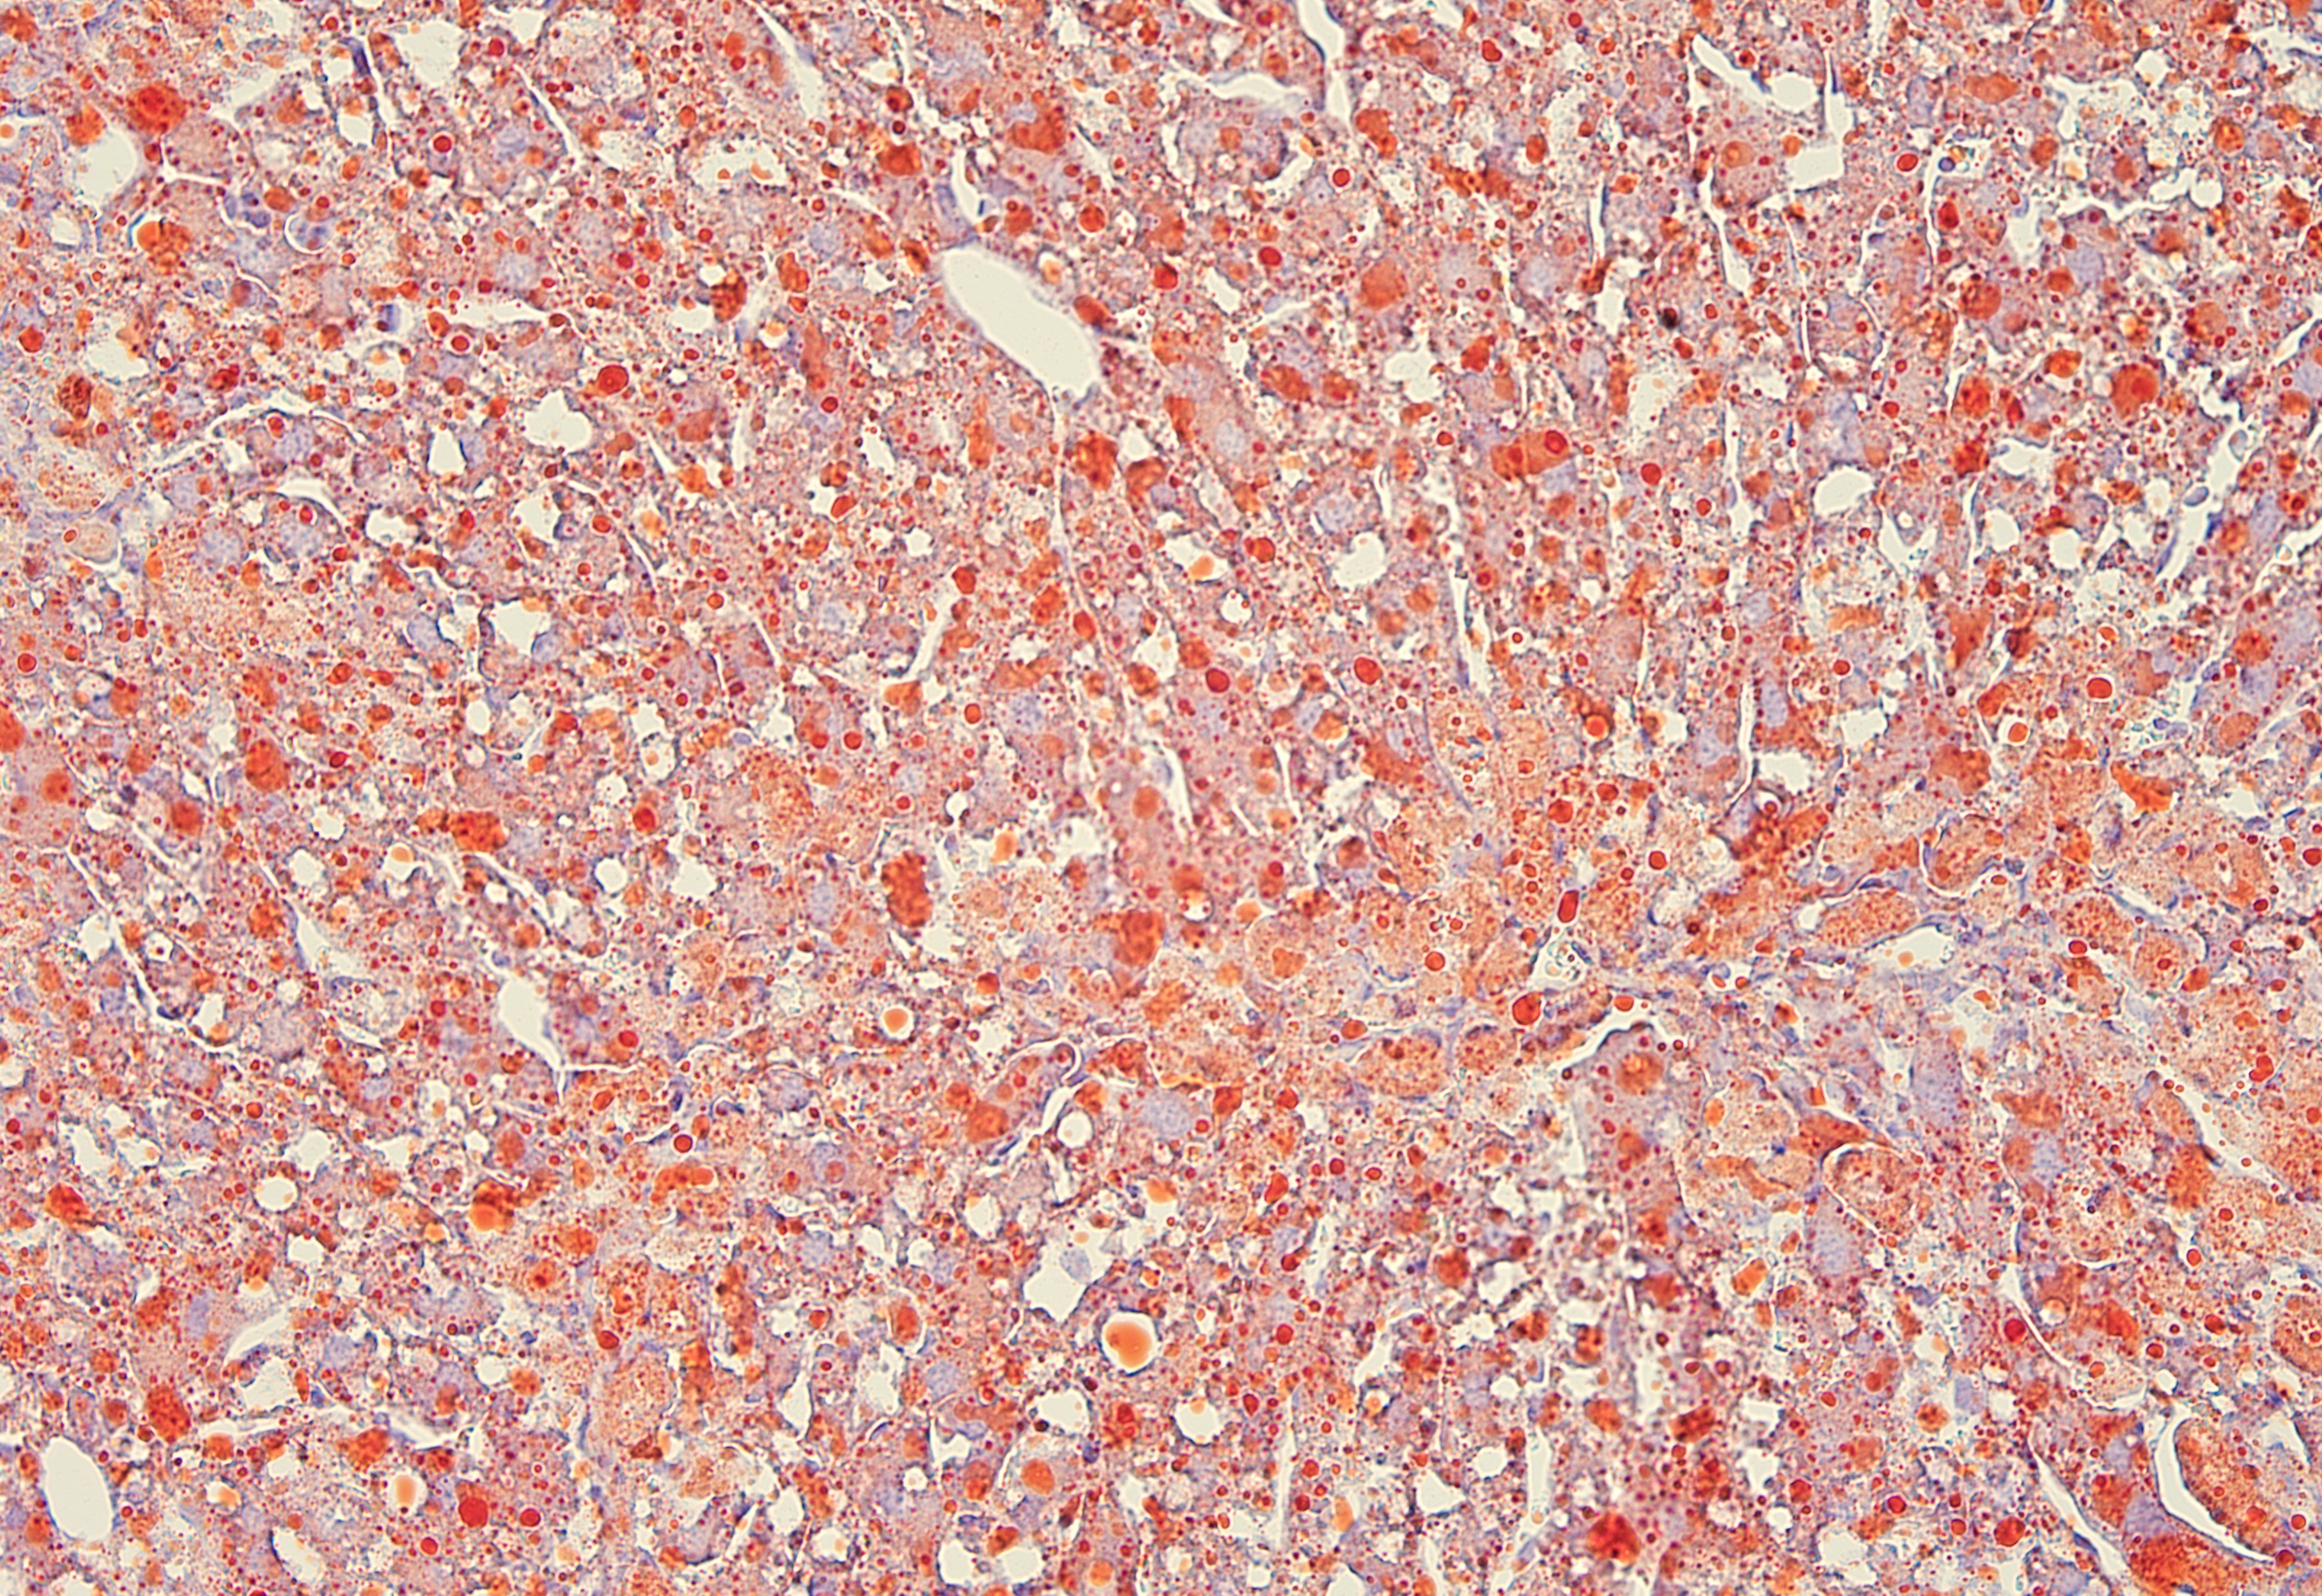

油红O染色

脂肪肝模型动物的肝脏油红    冰冻切片染色